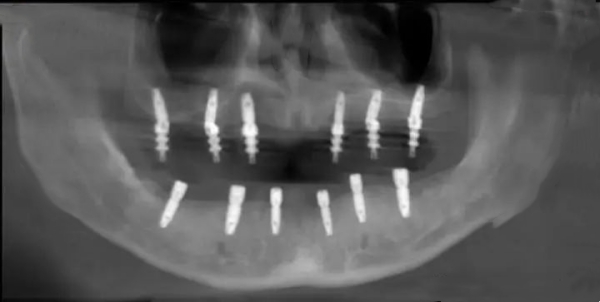

術(shù)后復(fù)查顯示,6顆種植體在顴骨內(nèi)的分布就像腳手架,力學(xué)分布非??茖W(xué)。